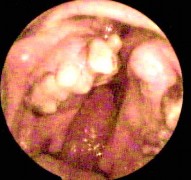

Hình ảnh nội soi tai

Ảnh 12 MN dính vào ụ nhô, khớp đe đạp MSBA. 1901263977 |